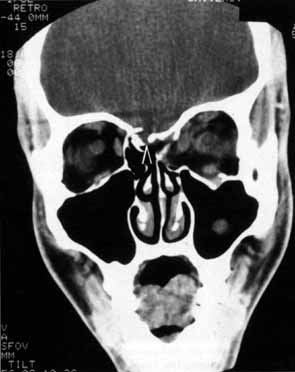

CRANIAL NERVE VII (FACIAL NERVE) Cranial nerve VII has no intraorbital component and so is rarely affected by pure orbital disease. However, damage to cranial nerve VII can result in orbital findings which aid in localization. Examples include the decreased reflex tearing of intra-cranial or proximal seventh cranial nerve damage, lagophthalmos associated with myotonic and muscular dystrophy, and essential blepharospasm. Seventh cranial nerve function may also be damaged by orbital surgery. Neurosurgical coronal flaps can produce weakness of the frontalis branch of cranial nerve VII if the incision is carried too far over the zygomatic arch, elevation is too superficial, or extensive traction is applied to the flap. Branch nerve palsy of cranial nerve VII can also occur if a lateral orbitotomy incision is carried too posterior over the zygomatic arch. CRANIAL NERVE I (OLFACTORY NERVE) Anosmia caused by damage of cranial nerve I may be a helpful symptom of ethmoid or sphenoid sinus tumors invading the orbit (Fig. 20).44 Olfactory groove meningiomas and esthesioneuroblastomas may also present with anosmia prior to developing vision loss.45 Trauma that involves the orbit and is associated with anosmia should be considered a basilar skull fracture with potential for cerebrospinal fluid leak until proven otherwise (Fig. 21). |